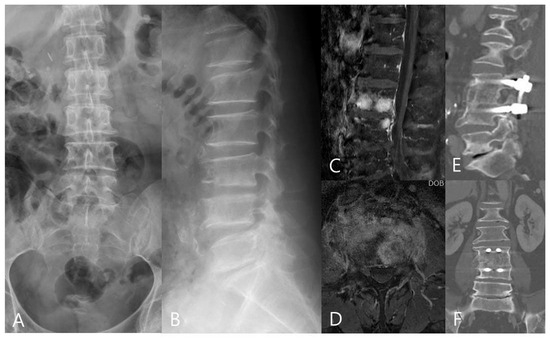

3.2. Radiographic Outcomes